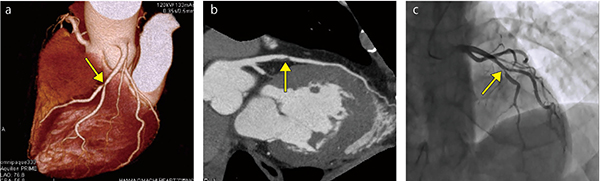

■Aquilion PRIME/Focus Editionによる冠動脈CT

69歳、男性 a:VR画像、b:CPR画像、c:血管撮影画像

早足歩行時に胸部に軽い圧迫感、動悸を主訴として来院。スクリーニングとして冠動脈CTを施行した。心電図ではST変化なしであったが、冠動脈CTではLADに高度狭窄を認めた(↑)。